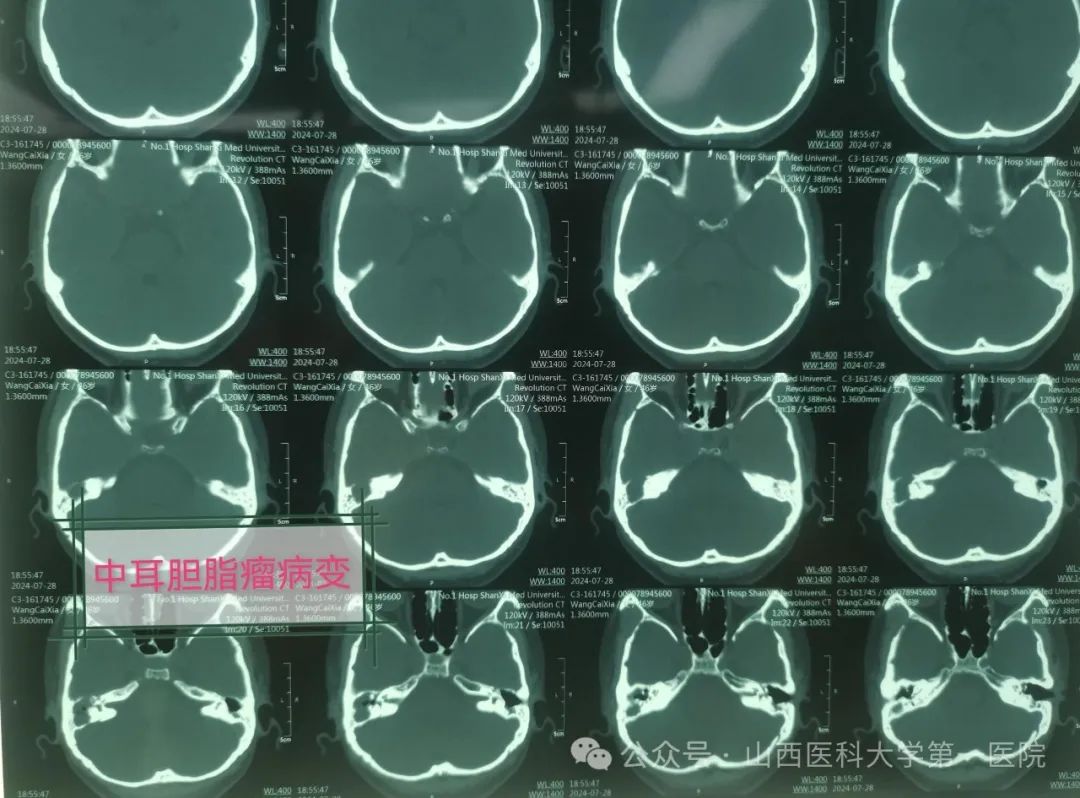

今年46岁的张女士,既往有中耳炎病史,最近半年多以来发现单侧耳总是流水,感冒发炎后加重,伴有听力减退,有时出现偏头痛,对症药物治疗效果不佳,最近1月余,症状逐步加重,同时出现头闷与头昏,甚至有走路失衡情况,并出现进行性面瘫现象,就诊于东京热

耳鼻咽喉-头颈外科,做影像学相关检查后被医生确诊为中耳胆脂瘤、面神经麻痹、迷路炎与迷路瘘管、局限性脑膜炎。

主刀医生张海利教授介绍,慢性化脓性中耳炎属于耳科常见疾病,而中耳炎胆脂瘤属于其中较为危险的一种类型。胆脂瘤并非平时所说肿瘤,是位于中耳与乳突腔内囊性结构,有脱落上皮细胞堆集、中央坏死,像滚雪球一样,越聚越大而形成。胆脂瘤患者临床上可出现耳流脓、耳痛、耳闷塞感及听力下降等症状,耳流脓一般呈持续性或间断性,有特殊恶臭味,有时伴有血性分泌物。胆脂瘤具有潜在危害,逐渐增大时会压迫并侵蚀周围骨质,并向邻近组织扩散,严重者可出现脑膜炎、眩晕以及面瘫等颅内外并发症。此例中年女性患者胆脂瘤破坏范围较大,中颅窝脑板已经破坏,形成局限性脑膜炎并发症,而且现在已有偏头痛的症状,同时在手术中发现内耳水平半规管与后半规管破坏,形成迷路瘘管与迷路炎,面神经骨管裸露破坏,医生在显微镜下仔细清理病变组织包括胆脂瘤与肉芽组织,经过乳突根治、面神经减压以及内耳迷路修补治疗,手术获得圆满成功。术后,张女士病情得到基本控制,经过消炎消肿抗感染以及对症治疗后即可出院。